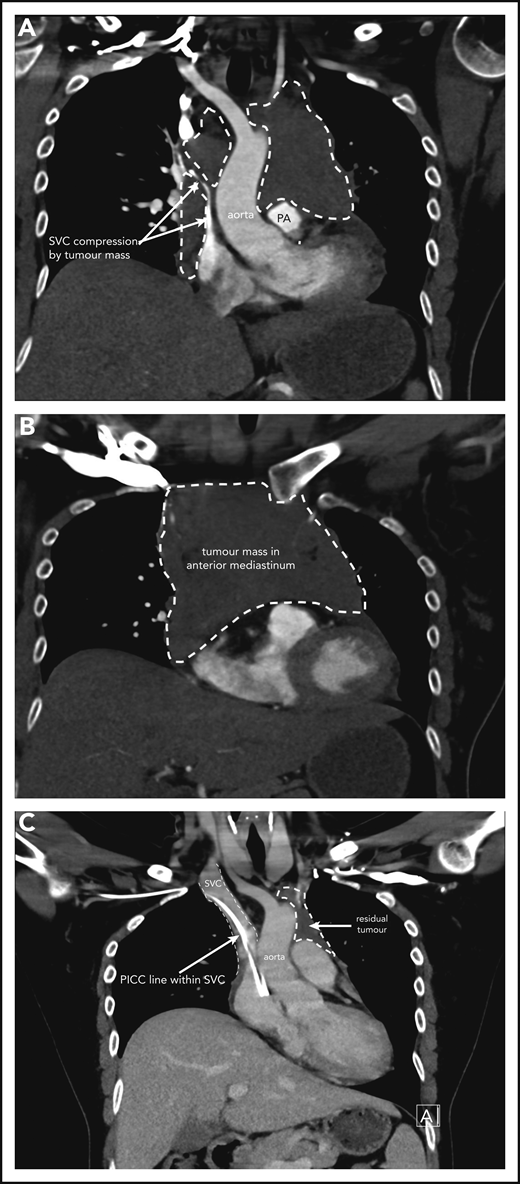

A 37-year-old woman, in her second ongoing pregnancy, presents to the emergency room at 30 weeks and 6 days (30+6 weeks) gestation with a history of chest pain and shortness of breath that woke her from sleep. She also has cramps in her right calf. She has been experiencing increasing shortness of breath and palpitations when mobilizing over a few weeks. She is a nonsmoker who drinks no alcohol. There are no concerns with her baby, and her first pregnancy and birth were uncomplicated. On examination, she is tachycardic at 120 beats per minute, normotensive with a blood pressure of 114/60 mm Hg, oxygen saturations of 97% on room air, and afebrile. Distended jugular veins are noted bilaterally, and she has no chest wall tenderness. Chest auscultation revealed crackles in the right lower zone. Heart sounds are dual with no murmurs. She has no lymphadenopathy, and abdominal examination reveals an enlarged uterus as expected for her dates with no other abnormalities. Complete blood count is normal. A comprehensive metabolic panel is normal other than an elevated lactate dehydrogenase (448 U/L; reference range, 120-250 U/L) and C-reactive protein (70 mg/L; reference range, 1-5 mg/L). The initial clinical concern for a pulmonary embolism prompted a computed tomography (CT)-pulmonary angiogram. This shows a large mediastinal mass measuring 11.5 × 8.3 × 8.3 cm causing significant obstruction of the superior vena cava and left main pulmonary artery and narrowing of the left upper lobe bronchi (Figure 1A-B). A small pericardial effusion is noted. Differential diagnosis includes lymphoma with other possibilities of thymic neoplasm, teratoma, or thyroid malignancy. A CT-guided biopsy of the mediastinal mass is performed and confirms focal areas showing proliferation of medium to large lymphoid cells. The large lymphoid cells are positive for CD20, CD79a, and PAX5, as well as BCL6, and have weak BCL2 staining. CD23 and CD30 show weak patchy positivity in the large cells and CD10, CD15, MUM1, cyclin D1, and Epstein-Barr virus in situ hybridisation (ISH) are negative. The Ki67 proliferative fraction is 60%. Fluorescence in situ hybridization studies reveal no rearrangement of MYC, BCL2, or BCL6. Pathologic features are consistent with a diagnosis of PMBCL.

Case 1 of patient with primary mediastinal B-cell lymphoma presenting at 31weeks gestation. (A) Coronal section chest CT scan with contrast at diagnosis, pretreatment. Illustrates significant compression of SVC by tumor mass (within broken lines) on right and demonstrating extent of mass also on left superior to pulmonary artery (PA). (B) Transverse section chest CT scan with contrast at diagnosis, pretreatment. Illustrates extent of anterior mediastinal tumor mass. CT imaging suggested possible moderate-sized pericardial effusion found on echocardiography to be a small effusion. (C) Coronal section chest CT scan with contrast at completion of treatment. Normal caliber SVC with a peripherally inserted central catheter (PICC) line in situ. Small volume of residual tumor (within broken lines). Subsequent PET-CT scan demonstrated no activity confirming a complete metabolic response.

The patient initially received high-dose steroids for treatment of her SVC syndrome once the diagnosis was made. She then received her first cycle of DA-EPOCH-R therapy at 33+3 weeks of gestation and tolerated it very well. Additionally, growth colony-stimulating factor was administered with no complications. An MRI of the chest was performed 2 weeks later and showed reduction in the size of the mediastinal mass to 8.6 × 4.5 × 5.4 cm with significant improvement in SVC and airway compression. Labor was induced at 35+5 weeks, and our patient had an uncomplicated vaginal birth to a healthy girl (birth weight, 2585 g) who had no neonatal complications. She received her second cycle of DA-EPOCH-R on day 22 as per the chemotherapy regimen without complication on the fourth postpartum day and subsequently completed a total of 6 cycles of therapy. CT and FDG-PET scans were done at completion of therapy, showing significant shrinkage of the mass on CT (Figure 1C) and complete metabolic response on FDG-PET, and she did not require consolidation mediastinal radiation. She remains in complete remission at last follow-up.